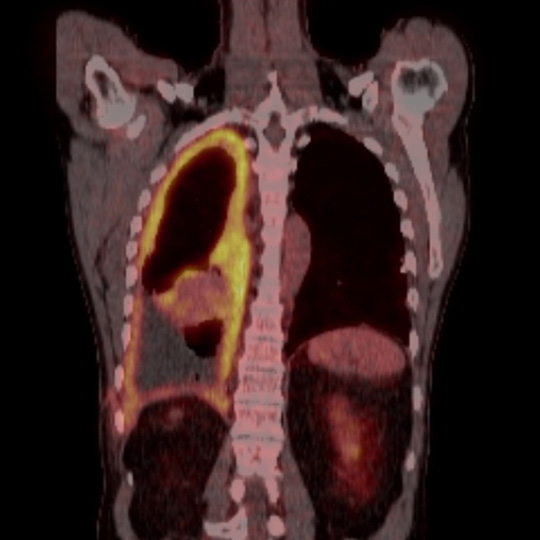

En mann i 60-årene ble utredet på bakgrunn av økende dyspné. Han hadde vært eksponert for asbest noen uker i 1970-årene, og hadde røykt fra 15 års alder. Det ble ikke funnet atypiske celler i pleuravæske. Diagnosen pleuralt mesoteliom ble fastsatt etter åpen pleurabiopsi. 18-fluorodeoksyglukose positronemisjonstomografi kombinert med computertomografi (18F-FDG PET/CT) ble rekvirert for å avklare om han kunne være kandidat for kirurgi.

18F-FDG tas opp i celler med høyt energibehov, som hjerte- og hjerneceller, betennelsesceller og maligne celler. Avbildning med PET/CT viser til venstre opptak i et malignt pleuralt mesoteliom med typisk utbredelse langs mesotelkledde hinner, her langs høyre pleura, inkludert lappespaltene. Til høyre viser CT alene de strukturelle forandringene i detalj, men skiller dårligere mellom viabelt tumorvev og benigne forandringer, som atelektase.

18F-FDG PET/CT gir mulighet for mer nøyaktig bestemmelse av sykdomsutbredelsen enn CT alene. Dette utnyttes blant annet til å selektere pasienter med begrenset sykdom for kirurgi. Ved pleurafortykkelse av ukjent årsak kan undersøkelsen være til hjelp i vurderingen av hvorvidt fortykkelsen skyldes malignitet. På grunn av lav oppløselighet har undersøkelsen imidlertid begrenset sensitivitet for små eller tynne maligne lesjoner (< 5 – 8 mm, avhengig av kamerateknologi). Tynne eller små maligne lesjoner i pleura inkludert i lappespalter kan derfor være PET-negative. Tykkere lesjoner uten opptak av 18F-FDG er mest sannsynlig benigne, selv om man må ta høyde for enkelte tumortyper som ikke tar opp stoffet.